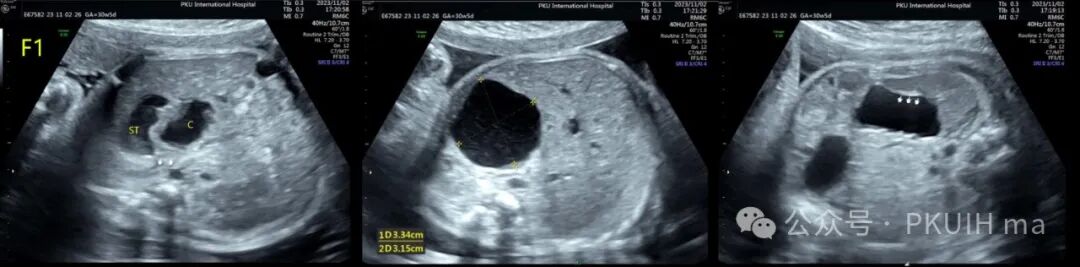

上图是一个单绒双羊双胎在孕30周发现胎儿胃旁囊性肿物,观察中可见大小有变化,同时可见胃壁结构,考虑胃重复畸形